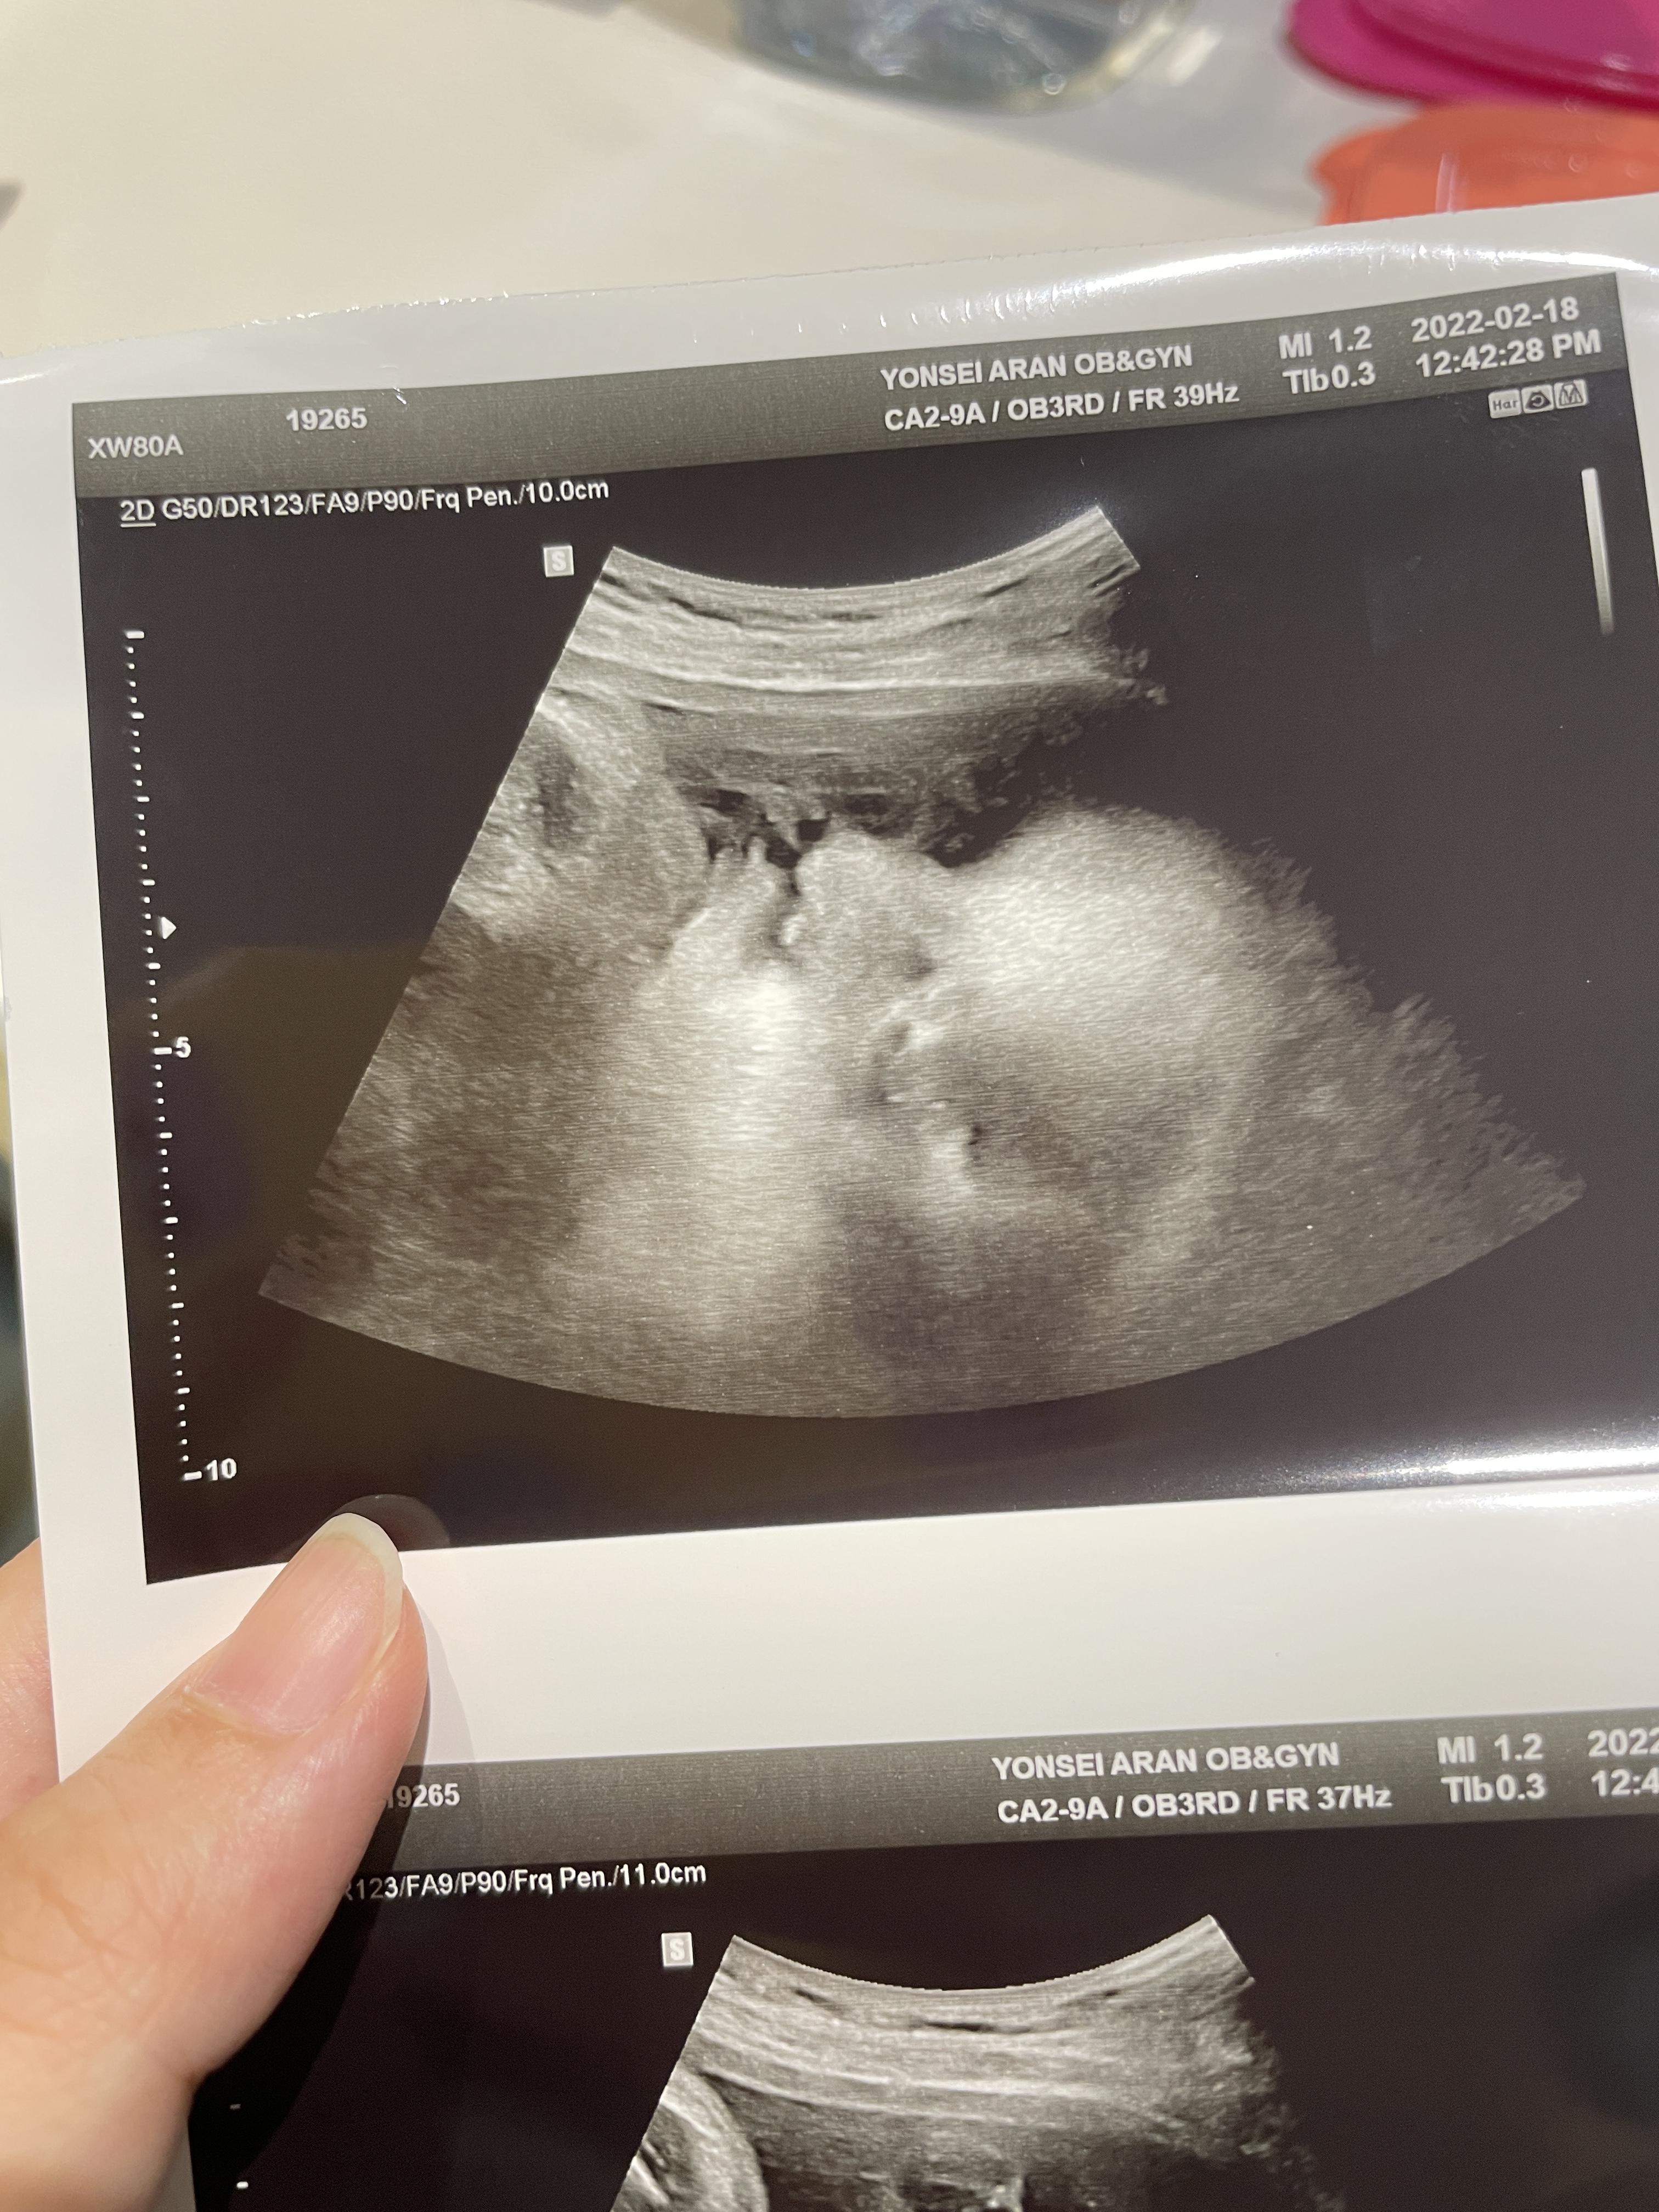

38주 1일차 진료

애기가 얼굴이 너무 잘보인다며 웃으셨다.

하나도 안내려왔다고...ㅠ

그와중에 머리는 역시 커졌고,